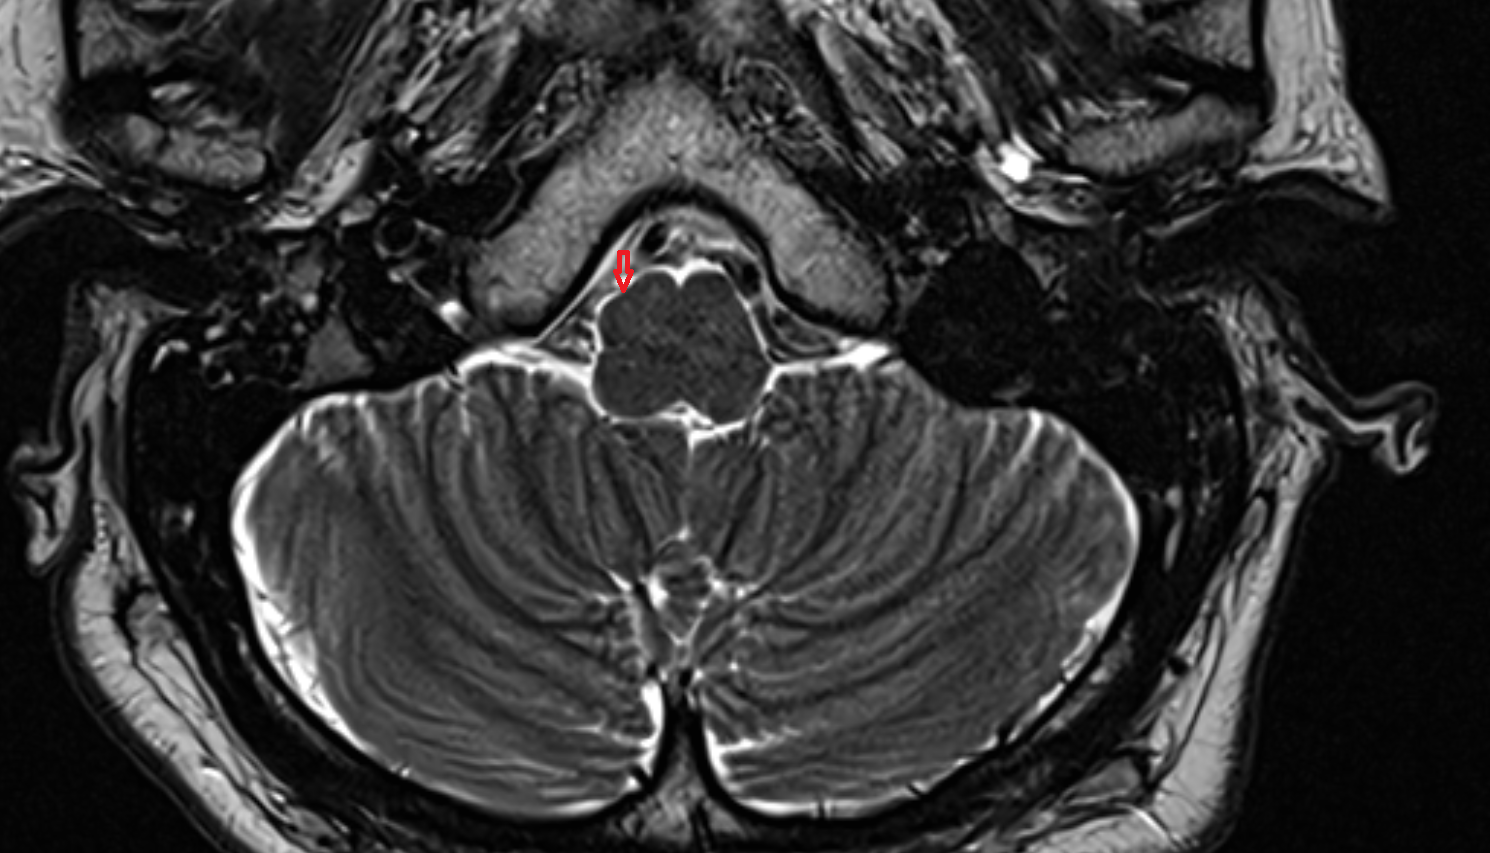

- Cerebellum

- Middle cerebellar peduncle